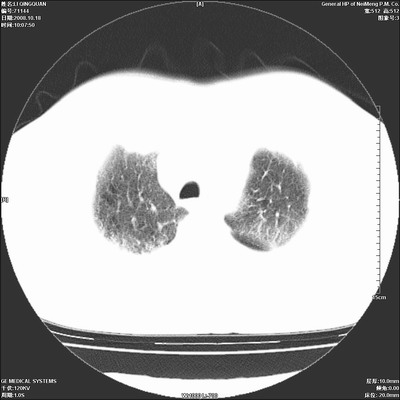

以下是引用duguo在2008-10-19 13:59:00的发言:[br]左肺上叶支气管狭窄,首先考虑中心型肺癌伴阻塞性肺炎\\肺不张.

以下是引用ybing在2008-10-19 12:58:00的发言:[br]左肺上叶阻塞性炎症-建议支气管镜进一步检查除外中央型肺癌

以下是引用随光逐影在2008-10-19 14:31:00的发言:[br]考虑左肺中央型肺癌并左肺上叶阻塞性肺炎,肺不张。